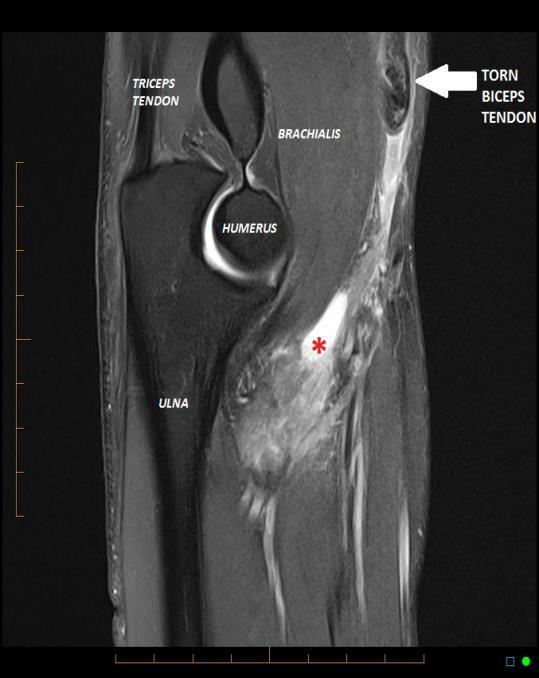

MRI •

Confirms biceps tendon rupture and locates the tendon stump, similar to ultrasound imaging

MRI provides greater sensitivity than ultrasound for partial and complex tears which may assist surgical planning

Multiplanar imaging of bone, cartilage and soft tissues in exquisite detail provides concurrent assessment of other alternative pathology, such as tendinosis, tenosynovitis, brachialis injury as well as ligamentous and osteochondral damage elsewhere in the elbow

Fig. 5 Sagittal MR showing rupture of the biceps tendon with the tendon retracted proximally and bunched above the elbow joint line (white arrow). There is fluid in the tendon defect with surrounding oedema (red asterix).

Fig. 7 Axial MRI showing rupture of the distal biceps. The tendon is absent from the radial tuberosity (red arrow). The bicipital aponeurosis has also torn causing subcutaneous and deep fascia oedema over the medial forearm (blue arrows). OTHER DISTAL BICEPS PATHOLOGIES